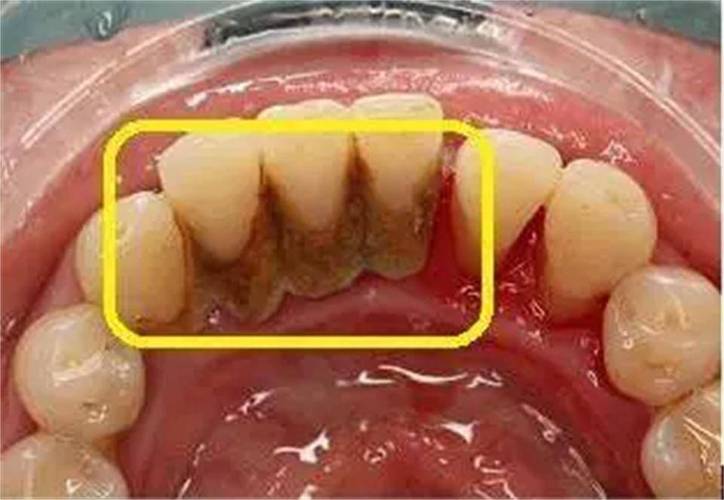

牙结石的形成是一个渐进的过程,始于牙菌斑的形成,牙菌斑是口腔中细菌与食物残渣、唾液成分混合形成的黏稠薄膜,附着在牙齿表面,尤其在牙龈边缘、牙面不易清洁的部位(如后牙的咬合面、牙齿邻面)更容易堆积,如果牙菌斑未能通过及时刷牙、使用牙线等方式被清除,它会与唾液中的矿物质(如钙、磷离子)结合,逐渐矿化变硬,形成牙结石,这一过程通常需要几天到几周的时间,初期呈软垢状,质地较软,颜色为乳白色或淡黄色,随着矿化程度增加,质地逐渐变硬,颜色加深,最终形成坚硬的牙结石,牙结石根据沉积位置可分为龈上结石和龈下结石:龈上结石位于牙龈缘上方,肉眼可见,通常呈黄色或棕色;龈下结石则位于牙龈缘下方,牙周袋内,颜色较深,呈褐色或黑色,且质地更坚硬,对牙周组织的危害更大。

牙结石对口腔健康的危害是多方面的,首先是引发牙龈炎,牙结石长期堆积在牙龈边缘,会不断刺激牙龈组织,导致牙龈充血、红肿、易出血,刷牙或咬硬物时出血是牙龈炎的典型表现,若不及时治疗,牙龈炎会进一步发展为牙周炎,牙结石中的细菌及其毒素会破坏牙周韧带和牙槽骨,导致牙周袋形成、牙龈萎缩、牙槽骨吸收,最终使牙齿松动、移位,甚至脱落,牙结石还可能影响美观,尤其是龈上结石明显时,会导致牙齿表面发黄、发黑,影响个人形象;长期存在的牙结石还可能引发口臭,因为细菌分解食物残渣会产生硫化物等异味气体。